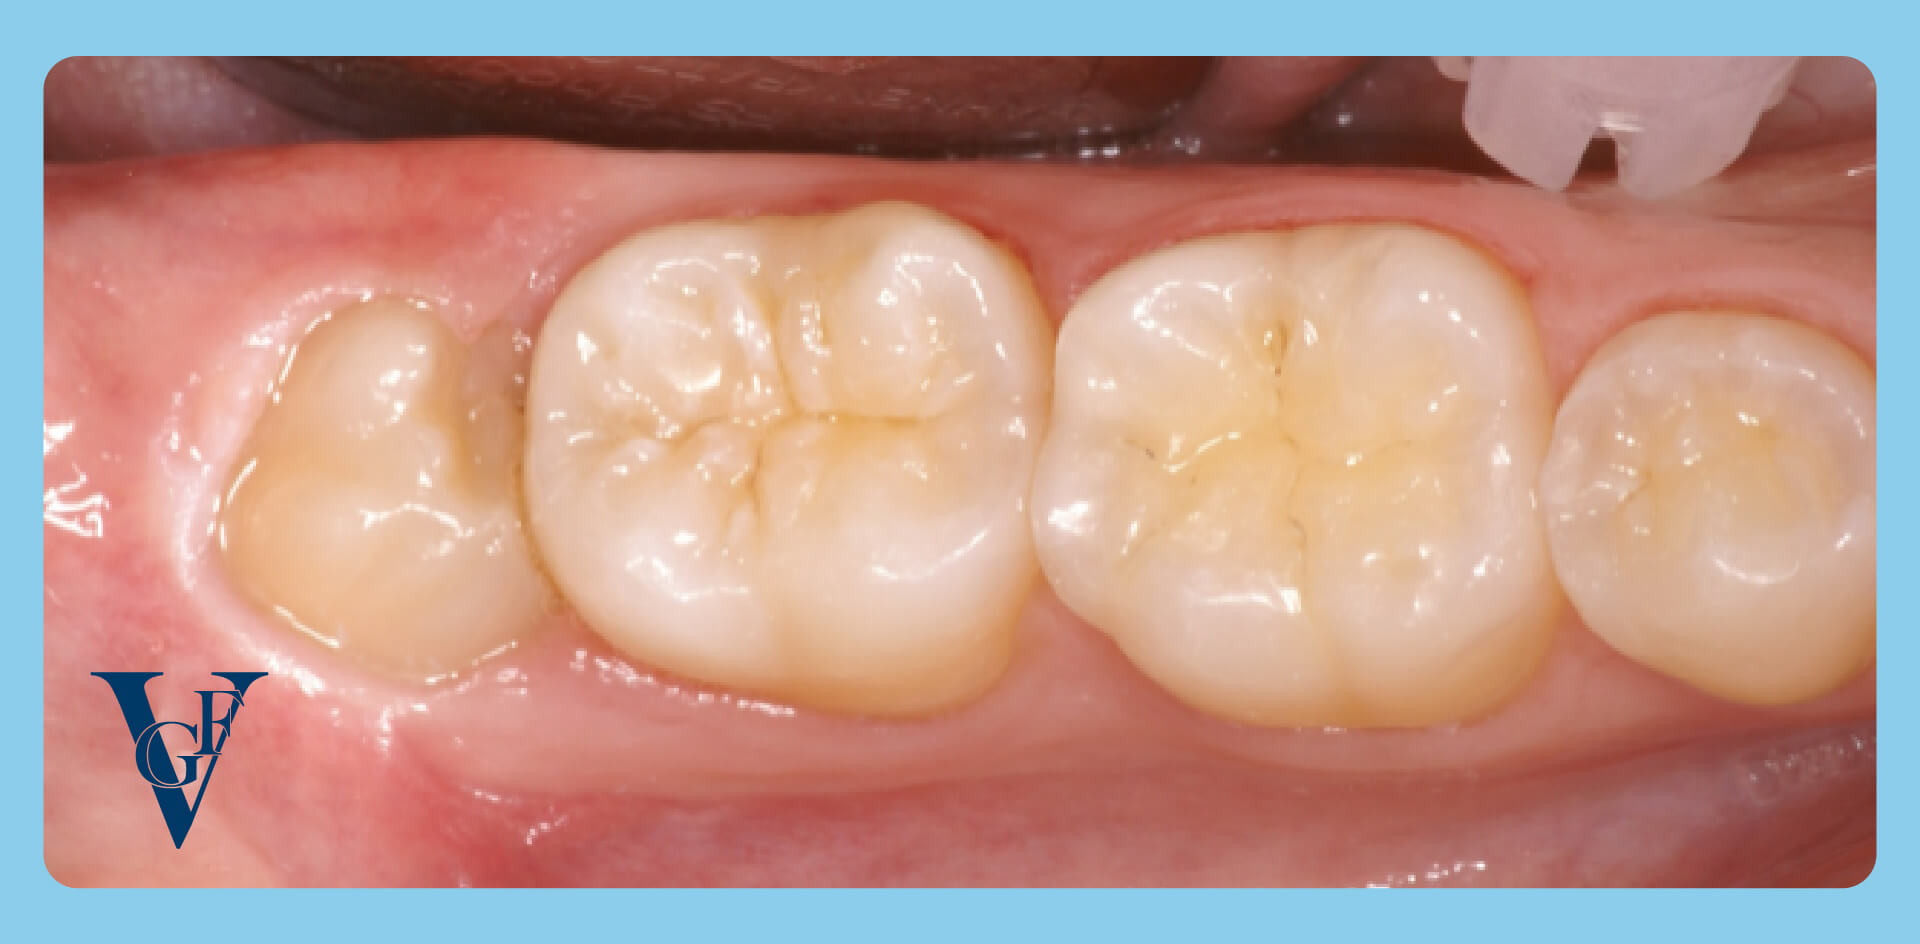

Nel primo caso si crea una situazione abbastanza complessa (che spesso richiede l’estrazione): la corona del dente è fuori dall’osso, ma resta in parte sotto la gengiva.

La conseguenza è la formazione di una “sacca” tra gengiva e dente, difficile da pulire correttamente per la sua posizione.

La zona tende a infiammarsi: a volte resta silente per anni, altre volte evolve in una gengivite ricorrente o pericoronarite, fino ad arrivare a un ascesso.

Il dente del giudizio in posizione non corretta può avere delle conseguenze sul dente davanti (il secondo molare). In quella posizione scorretta è facile che si incastri il cibo, favorendo così l’accumulo di placca e conseguentemente la formazione di carie.